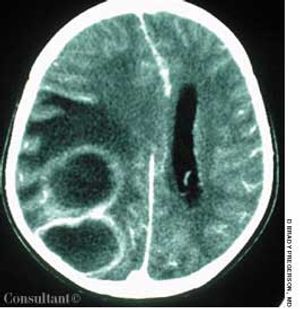

While playing outside, a 23-month-old girl became sleepy and difficult to arouse. The mother brought her daughter to the emergency department (ED); posturing and a dilated and fixed right pupil were noted. The child was hospitalized.